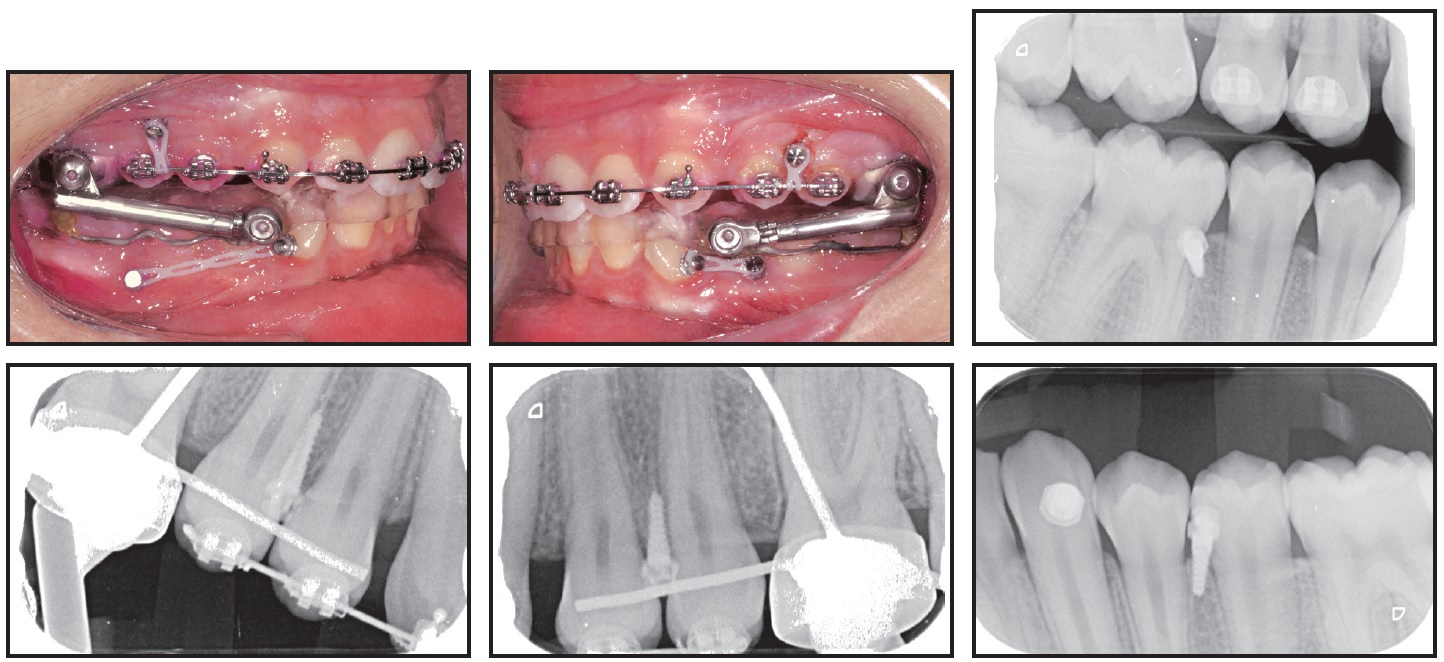

Preadjusted .022" × .028" brackets*** were placed in the upper arch, and an .014" nickel titanium archwire was used to correct the upper incisor inclination and the scissor bite (Fig. 2). After five months of treatment, a Herbst appliance with four 1.4mm × 6mm TADs† (H4T) was placed (Fig. 3). In the lower arch, one miniscrew was inserted between the right first permanent molar and second premolar and the other between the left first and second premolars. Auxiliary buttons were bonded to the buccal surfaces of the canines, and elastic chains were attached to the miniscrews to retrocline the lower incisors and promote mandibular protraction. In the upper arch, a miniscrew was inserted between the first and second premolars on each side, and elastic chains were attached between the miniscrews and an .018" × .022" stainless steel archwire for vertical control.

Fig. 4 Failed upper left TAD replaced after 11 days with TAD between canine and first premolar.

Fig. 5 Herbst appliance removed after 10 months of treatment.

The upper and lower arches exhibited an overcorrected Class I relationship. The upper first molars were bonded, and an .017" × .025" nickel titanium archwire was inserted (Fig. 6). Fixed multibracket appliances with .016" × .025" nickel titanium archwires were then placed in the lower arch, and the patient was given light Class II elastics to wear full time, starting at 30g per side and increasing over 11 months to 250g per side. To mesialize the upper posterior segments, elastic chains were connected from the first molars to the miniscrews. The lower archwires progressed to .017" × .025" nickel titanium, followed by final upper and lower .018" × .022" stainless steel wires.

Fig. 6 Brackets bonded in lower arch, and full-time Class II elastic wear started; elastic chains attached between TADs and first molars to mesialize upper posterior segments.